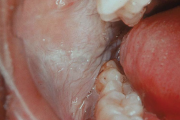

keemiline ärritus - alkoholist